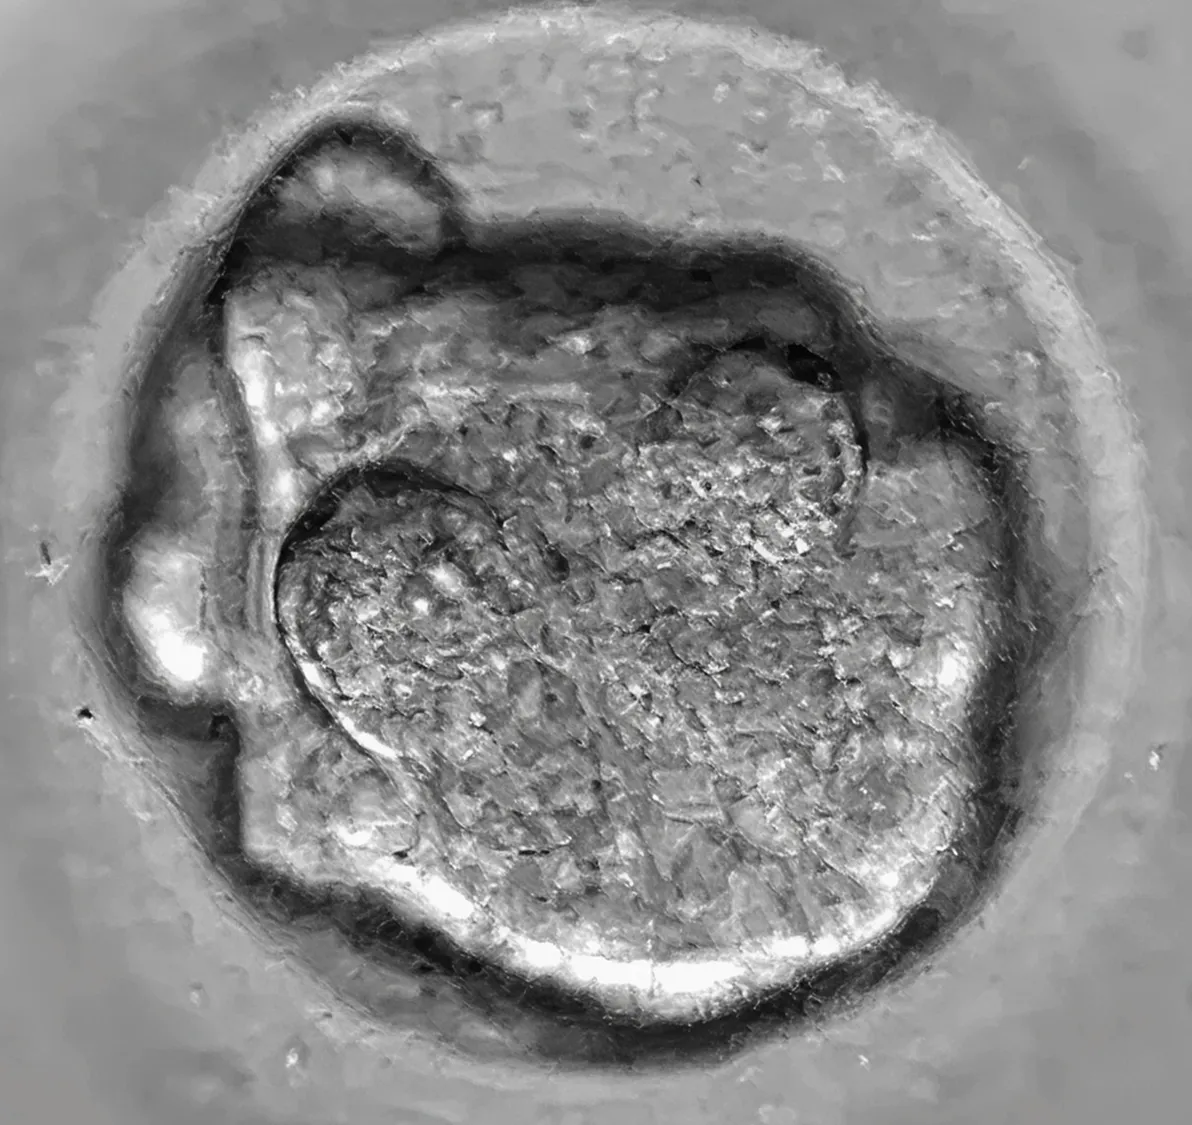

Морула

Клетките започват да се сливат и уплътняват – ембрионът придобива вид на малка „къпина“ – нарича се морула (от латинското morus – черница). Вътрешните и външните клетки вече започват да се специализират – първите ще станат бъдещият ембрион, а външните – плацентата.

Какво се вижда? – но този етап клетките вече не се виждат поотделно – започва специализацията им; ембрионът изглежда по-компактен и светлината се отразява различно върху повърхността му.

Бластоцист

Ембрионът вече е съставен от 100-120 клетки и вече е много по-голям. Обвивката (Zona pellucida) е много изтъняля, защото ембрионът се готви да се „излюпи“ от нея.

Какво се вижда? – На екрана се появява нова структура – бластоцист. В центъра ще забележите малка светла кухина– това е бластоцела, а по периферията – тънък слой клетки (трофектодерм), който ще даде началото на плацентата. От едната страна има плътна група от клетки – вътрешна клетъчна маса, от които ще се развие бебето.